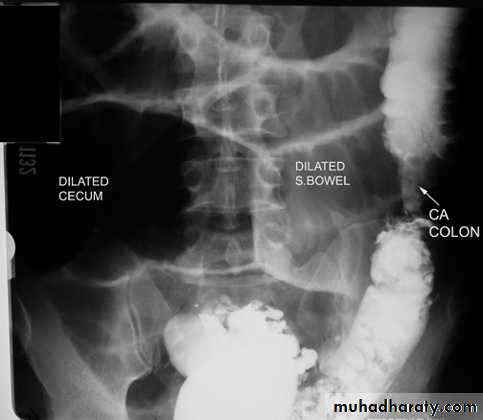

Colorectal carcinoma (CRC) is the most common cancer of the gastrointestinal tract and the second most frequently diagnosed malignancy in adults.

Clinical

o Peak age 50-70 years

o Weight loss

o Blood in stool

o Loss of appetite

o Change in bowel habits

Location

o Rectum (15%), sigmoid (20%), descending colon (10%), transverse colon (12%), ascending colon (8%), cecum (8%)

o More common in right colon with advancing years

o More common in left colon with chronic ulcerative colitis

Imaging findings

o 90-95% rate of detection by BEo Polypoid filling defect

o Annular constricting >>>>> apple-core lesion

Bowel obstruction

Plain x ray SBOdilated loops with air fluid level in erect position

centrally placed

transverse lines (circular folds ) valvule convent's

Plain x ray LBO

dilated bowel with gasperipheral

haustra (not lines across bowel)

may have cut-off point